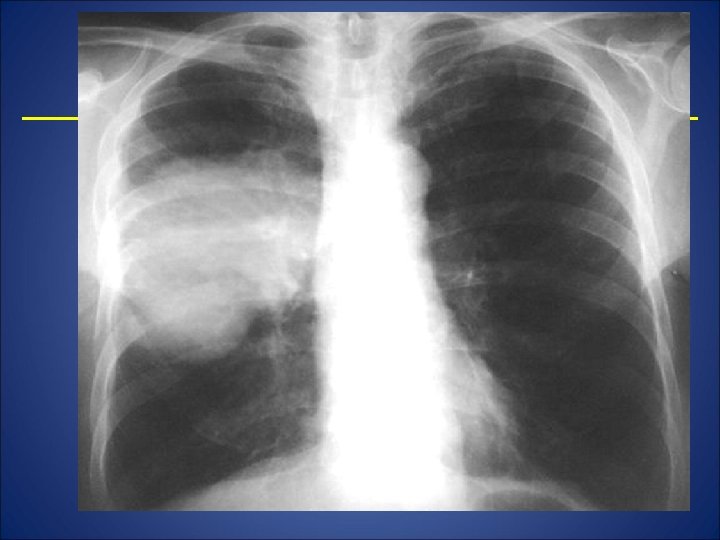

Radiografie pulmonara

EXAMENUL PARACLINIC • RADIOGRAFIA PULMONARA - in faza de constituire: opacitate intensa, omogena, slab delimitata de parenchimul din jur - In faza de evacuare: cavitate cu perete gros, forma ovoida, nivel hidro-aeric • CT PULMONAR Permite diferentierea intre un abces periferic si un empiem pleural • BRONHOSCOPIA -obligatorie la pacientii peste 45 ani • BIOLOGIC - sindrom inflamator, anemie, hemoculturi, examen de sputa